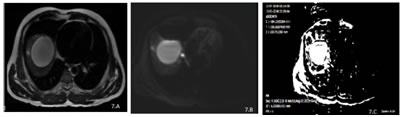

7

Figure 7-A, B, C: – A case of hydatid cyst of liver. Well defined hyperintense lesion in the right lobe of liver on axial T2eSSFSE sequence (A)with T2 shine through phenomenon on DWI sequence (B) and hyperintense signal intensity on ADC sequence.